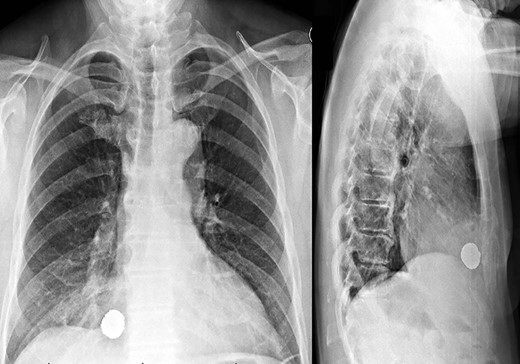

Representative coronal and sagittal images of the patient’s initial chest CT scan confirming the intrathoracic location of the foreign body with associated scatter due to its metallic contents.

A 59-year-old man was transferred acutely from another hospital for evaluation of a penetrating thoracic injury. The patient reportedly had been shot twice with a bean bag gun and sustained injuries to the right chest and flank during an altercation with police officers. The patient was breathing comfortably and normotensive, and his GCS was 15. He had a history of unprovoked pulmonary embolism and was taking apixaban. There was a 2-cm circular wound through the skin just superior to the right nipple and a 5-cm area of ecchymotic but intact skin over the right flank. A chest X-ray showed a 2-cm object with metallic density overlying the right thoracic cavity (Fig. 1). A chest CT showed the object in close proximity to the right atrium, right internal mammary artery and right middle lobe (Fig. 2). Additionally, a small amount of effusion consistent with hemothorax was present, for which a chest tube was placed. The patient was admitted for chest tube management and pain control, on the assumption that the metallic foreign body did not warrant operative removal.